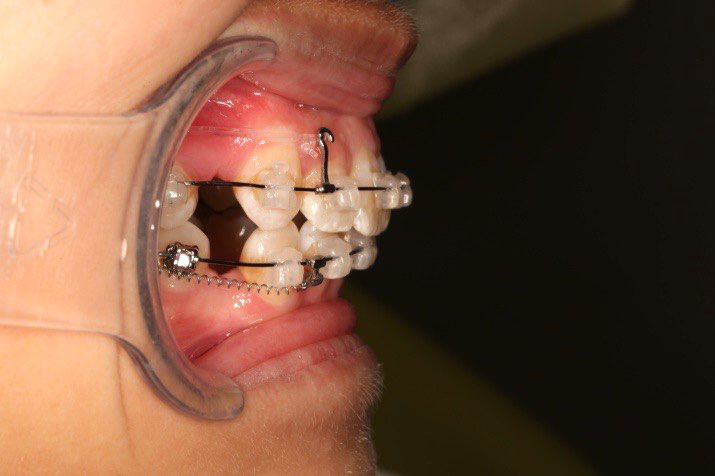

5.第7个月:2017.05.26 ◆ 下颌36/46加power arm

6.第9个月:2017.07.25 ◆ 上前牙加颈部弹力线

2017.05.26  磨牙近中倾斜,下颌36、46加power arm

下颌磨牙通过powerarm直立效果明显,下颌整平效果明显

下颌整平内收的生物力学

下前牙的压低+控制性倾斜移动内收,改善唇倾度,磨牙通过powerarm 直立,控根整体近中移动,使咬合高点的前移,整平下颌同时进行内收。